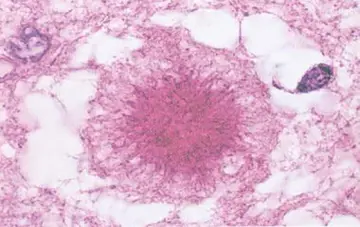

فاووس

شماره ۱۱۱۶